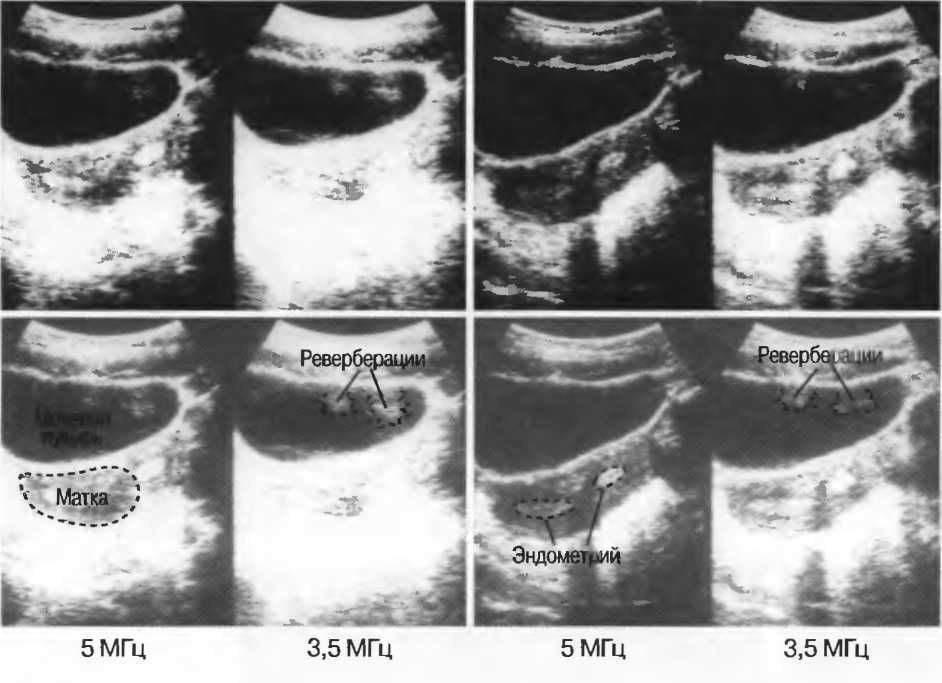

Затухание

Ткани тела поглощают и рассеивают ультразвук по-разному. Высокие частоты поглощаются и рассеиваются (гасятся) в большей степени, чем низкие. Поэтому, чтобы достичь более глубоких тканей, необходимо использовать более низкие частоты, так как менее вероятно, что эти волны затеряются при прохонодении через ткани. На практике оптимально использовать частоту около 3,5 МГц для глубокого сканирования у взрослых и частоту 5 МГц и выше для исследования более худых пациентов или детей. Частота 5 МГц и выше используется для исследования поверхностных органов у взрослых.

Высокие частоты дают более детальное изображение, но имеют меньшую проникающую способность.

Выбор соответствующего датчика

Наилучшим датчиком для общей практики является конвексный датчик с частотой 3,5 МГц с фокусировкой на расстоянии 7-9 см. Если такого датчика нет, необходимо наличие линейного секторного датчика с частотой 3,5 МГц. При необходимости исследования детей и худых взрослых желательно дополнить набор датчиком с частотой 5 МГц с фокусировкой 5-7 см.

1. Ультразвуковые исследования в акушерстве. Для общих исследований в акушерстве используется линейный или конвексный датчик с частотой 3,5 или 5 МГц с глубиной фокусировки на 7-9 см. Если закупается только один датчик, выбирайте датчик с частотой 3,5 МГц. Датчик с частотой 5 МГц предпочтителен на ранних сроках беременности. В поздние сроки беременности лучше использовать датчик с частотой 3,5 МГц.

2. Ультразвуковые исследования в общей практике. Если проводятся исследования в верхней части живота и таза у взрослых, в том числе и акушерские исследования, предпочтительнее выбор секторного или конвексного датчиков с частотой 3,5 МГц с глубиной фокусировки на 7-9 см.

3. Ультразвуковые исследования в педиатрии. Для детей необходим датчик с частотой 5 МГц с глубиной фокусировки на 5-7 см. При исследовании мозга новорожденного используется секторный датчик с частотой 7,5 МГц с глубиной фокусировки на 4-5 см (этот датчик также используется для исследования яичек и структур шеи у взрослых).